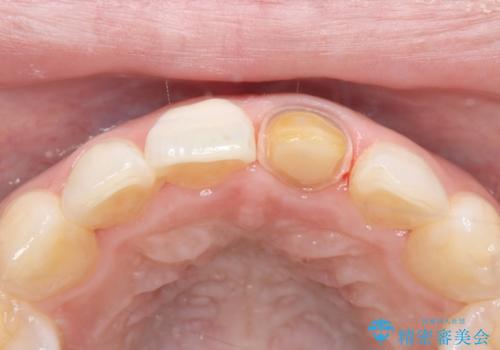

- 「以前、他院で神経を取った前歯がだんだん黒ずんできた」という見た目の改善を主訴にご来院されました。 診査の結果、神経を取り除いた後の歯(失活歯)特有の変色が起きており、さらに根の先端にわずかな影が見られたため、内部で感染が起きている可能性がありました。

そこで、まずは土台を外して根の内部をきれいにする再根管治療を行い、基礎をやり直した上で、透明感の高いオールセラミッククラウンで被せ直す治療計画を立案。単に白くするだけでなく、再発を防ぎ、長期的に美しい状態を保つことを目指しました。

土台(ファイバーコア)の構築: 金属の土台は将来的な変色の原因となるため、光の透過性が高く、歯のしなりに近い性質を持つファイバーコアを採用。これにより、被せ物の透明感を損なわず、歯の破折も防ぎます。